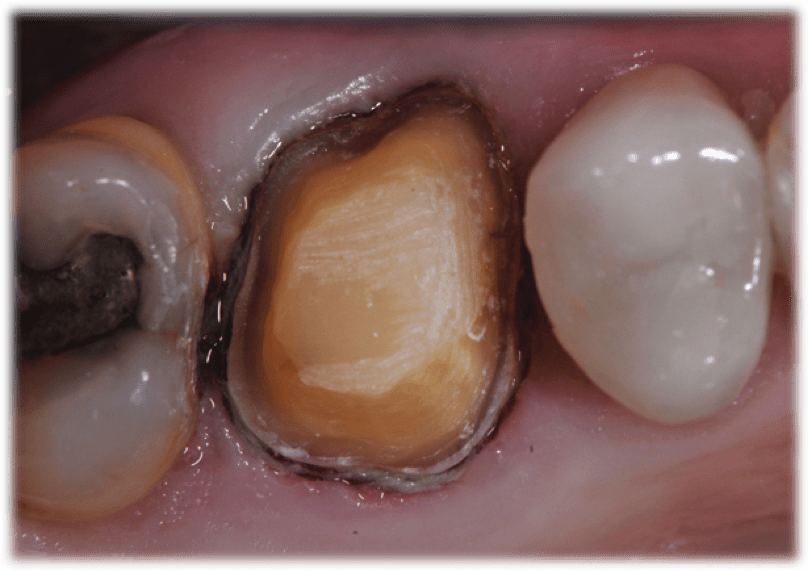

It should be noted that Premier’s KR Modified Shoulder prep burs allow for a 90° margin with a rounded internal angle. This combination of burs allows me to prepare crowns, inlays, or onlays, and serves as my first choice for a restorative bur block. After tooth preparation is complete, the dentist must address whether retraction is needed. Clinicians can either place a retraction cord or use a paste retraction system like Traxodent® Hemodent™. Typically, I use both retraction cord and Traxodent, which better isolates the preparation for scanning and designing a CAD/CAM milled restoration. It also isolates the tooth for same day seating of the restoration, keeps the area clean before the procedure, and assists in a fast, easy cleanup of bonding materials.

I create same-day restorations using the Planmeca PlanMillTM 40 to produce a precise, smooth and well fitting restoration (Figure 4). Once the restoration is milled and tried in the patient’s mouth, the Two Striper finishing kit allows for the clinician to make any desired finishing touches (Figure 5 and Figure 6). For in-mouth finishing, I prefer to use Solo diamond finishing burs. If minor adjustments are required, the Premier Diamond Twist extraoral polishing system can also be utilized prior to cementation.

In this case, patient radiographs (Figure 7 and Figure 8) demonstrate a well-fitting CAD/CAM restoration that began with proper preparation design using the Solo diamond and efficient milling with the PlanMill 40. These tools can help clinicians provide ideal chairside tooth preparation, digital impressioning, and CAD/CAM milling, to ultimately deliver restorations of the highest quality.